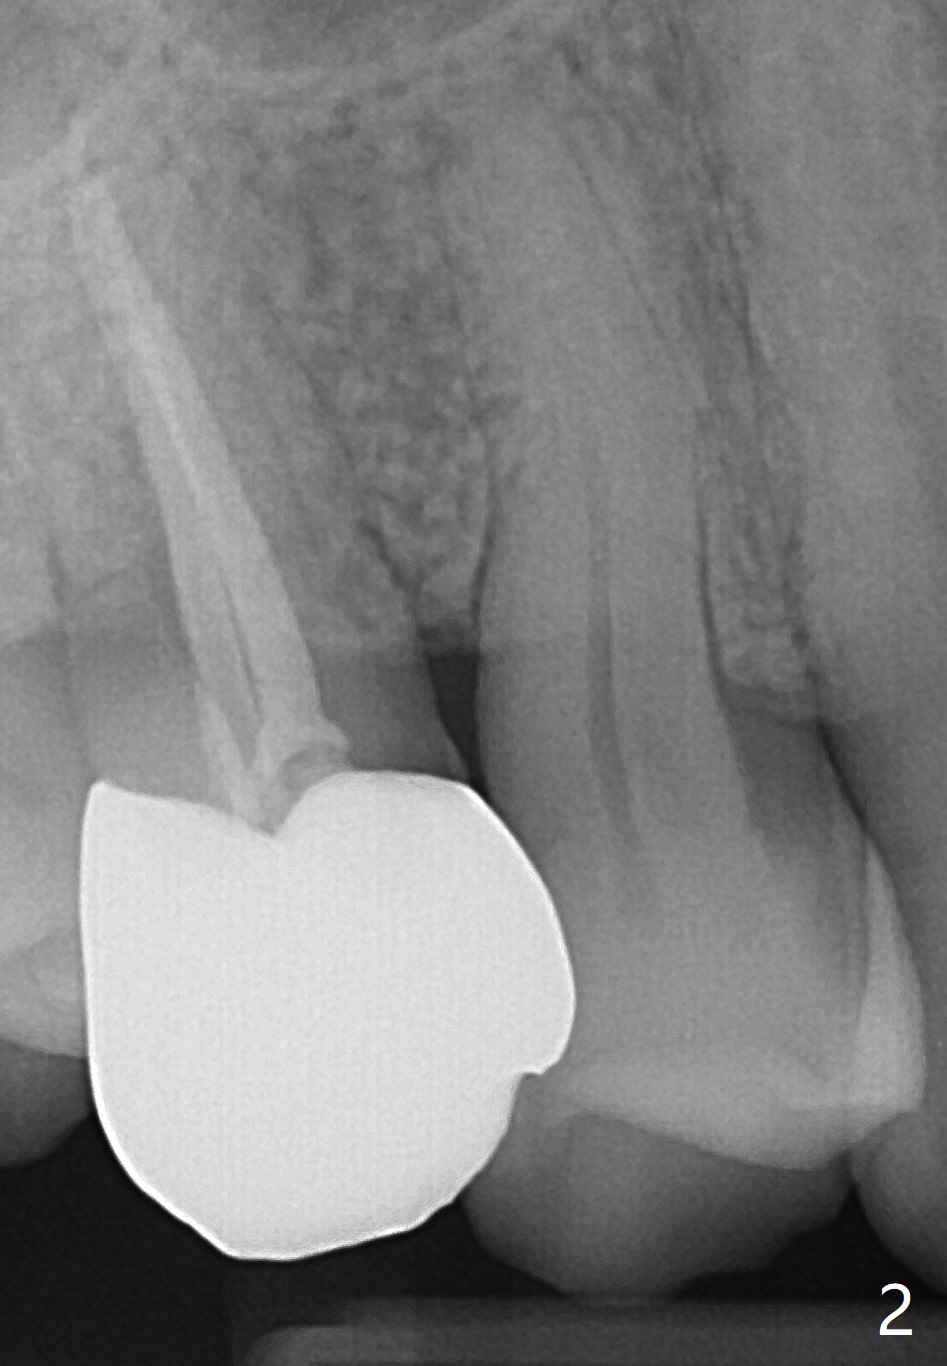

A 63-year-old man develops cold and hot sensitivity in the upper right 1st premolar after crack noise. The tooth #5 has a mesiodistal crack line (Fig.1-2). Two weeks later, the palatal cusp fractures subgingival. There is no time for guide (Fig.3). Since the root is curved and apparently difficult to extract, prepare surgical hand piece for socket shield.